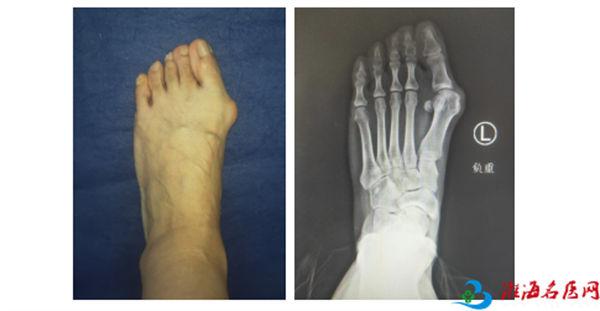

等到摄片结果出来,更是印证了曹主任的诊断。

黄阿姨的拇外翻已经到中度,并且严重的拇囊炎侵犯到跖趾关节,随着时间的推移,畸形会逐渐加重,需要进行手术治疗。这种手术在徐州仁慈医院仅需2个小切口就能解决侵扰黄阿姨十年的问题。